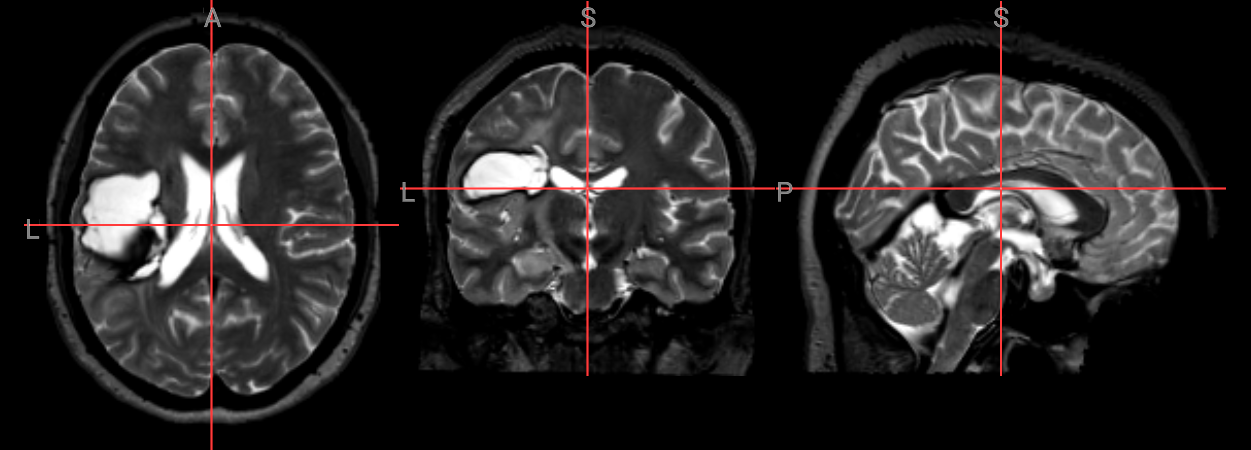

nv_mni_space = NiiVue()

nv_mni_space.load_volumes([{"url": "https://huggingface.co/datasets/neurodeskorg/neurodeskedu/resolve/main/data/examples/structural_imaging/SYNcro/wbt1sub-M2304_ses-262_acq-spc3p2_run-5_T2w_e75b1be55e40.nii.gz"}])

nv_mni_space

Image(filename='../../static/examples/structural_imaging/SYNcro/mni_wbt1sub-M2304.png')

../../_images/b06e50bae8f9d304f61721edceda4d061d8ea68eb193894135c895b2841df917.png